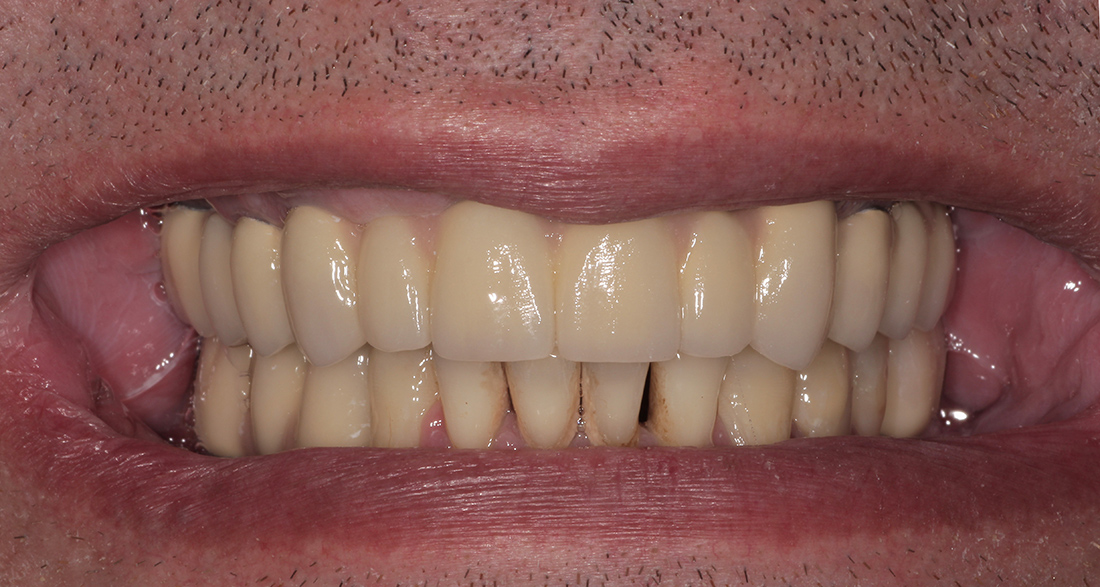

Окончательное протезирование было выполнено тремя металлокерамическими мостовидными конструкциями на верхней челюсти, мостовидным протезом внизу справа и отдельной коронкой на импланте в области шестого зуба нижней челюсти слева. Фиксация коронок проводилась на индивидуальные циркониевые абатмены одноэтапно.

Общий срок лечения составил порядка пяти месяцев.